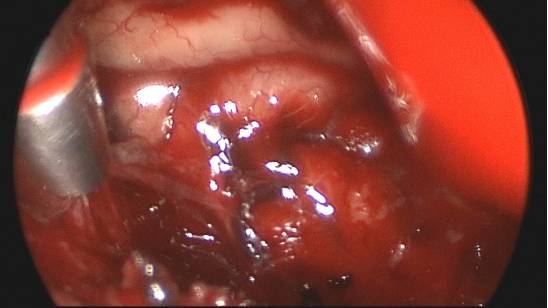

图6. 在切开天幕接近肿瘤的过程中,可通过锐性分离蛛网膜来充分暴露天幕游离缘的神经血管结构,早期的充分暴露能够避免在肿瘤切除过程中受到损伤。

充分锐性分离瘤旁的蛛网膜带会避免损伤滑车神经。

图15. 内镜可以在切除肿瘤时显微镜视线不及的地方进一步探查和继续切除,尤其是大脑镰后方和直窦附近的区域。岩尖部也可以通过有角度的内镜来进一步探查。